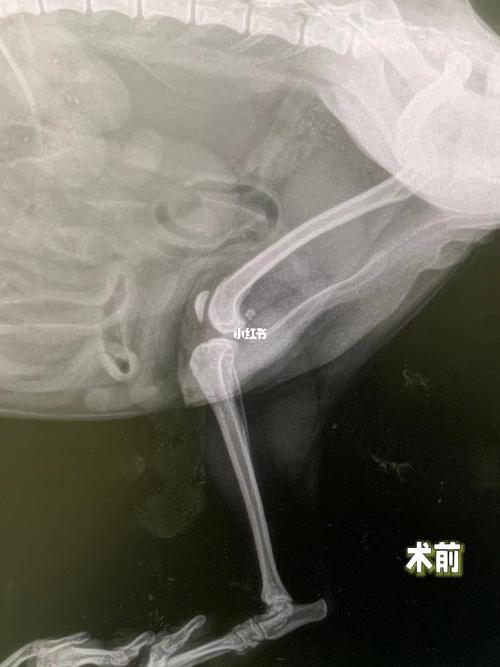

狗狗后腿韧带断了主要会出现后腿随意摆动、狗狗无法控制后腿运动、疼痛、无力等现象。狗狗后腿韧带断裂需要做核磁共振或者CT来确诊,如果狗狗的韧带确实断了,则根据狗狗的具体情况给狗狗做手术或者让狗狗静养让其自愈。

〖陆〗、首先狗狗的韧带断裂需要进过CT或者核磁才能做出诊断,具体的恢复时间依据损伤的严重程度而定。如果已经确定是韧带断裂,那基本不可以自愈,狗狗会出现永久性运动障碍,这种需要通过外科手段再造韧带或者使用人工韧带,手术后需要半年到一年的恢复期。